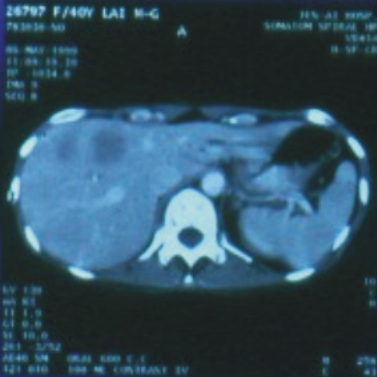

41歲/女性(膽道癌合併肝轉移) |

||

88/5/6(治療前) |

88/6/6 (治療後) |

腫瘤大小:4.5x4.5x4公分 |

完全消失 |